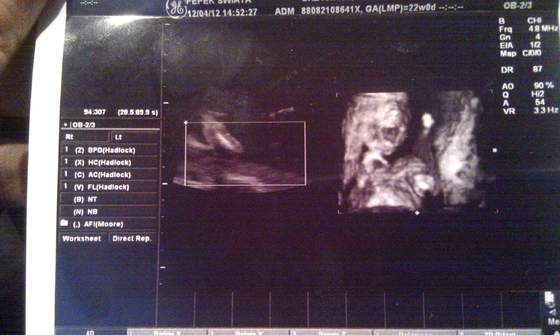

Dzidziuś pięknie wygląda, jest zdrowy, ruchliwy, ziewał sobie, pokazał pitoczka ze wszystkich stron (z tej okazji znów kupiłam dzisiaj kilka niebieskich ciuszków), nie wiem ile ma długości ale waży 310 gram, więc chyba do wielkoludów nie należy ale nie wiem bo się nie znam. Doktor mówił że wszystko jest ok, to znaczy że ok

oglądaliśmy wszystkie obszary mózgu, komory i przedsionki serca, oraz inne organy wewnętrzne. Najfajniej jednak wyglądały stópki :-)